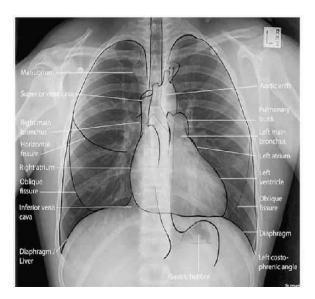

Diagnostic Imaging: CXR systematic approachs

Use a systematic approach

• Airway Structures

Trachea, Carina, Bronchi

• Breathing Structures

Lungs, Pleura

• Cardiac

Heart size, borders

• Diaphragm

Costophrenic angles

• Everything else

Aorta, bones, tissue